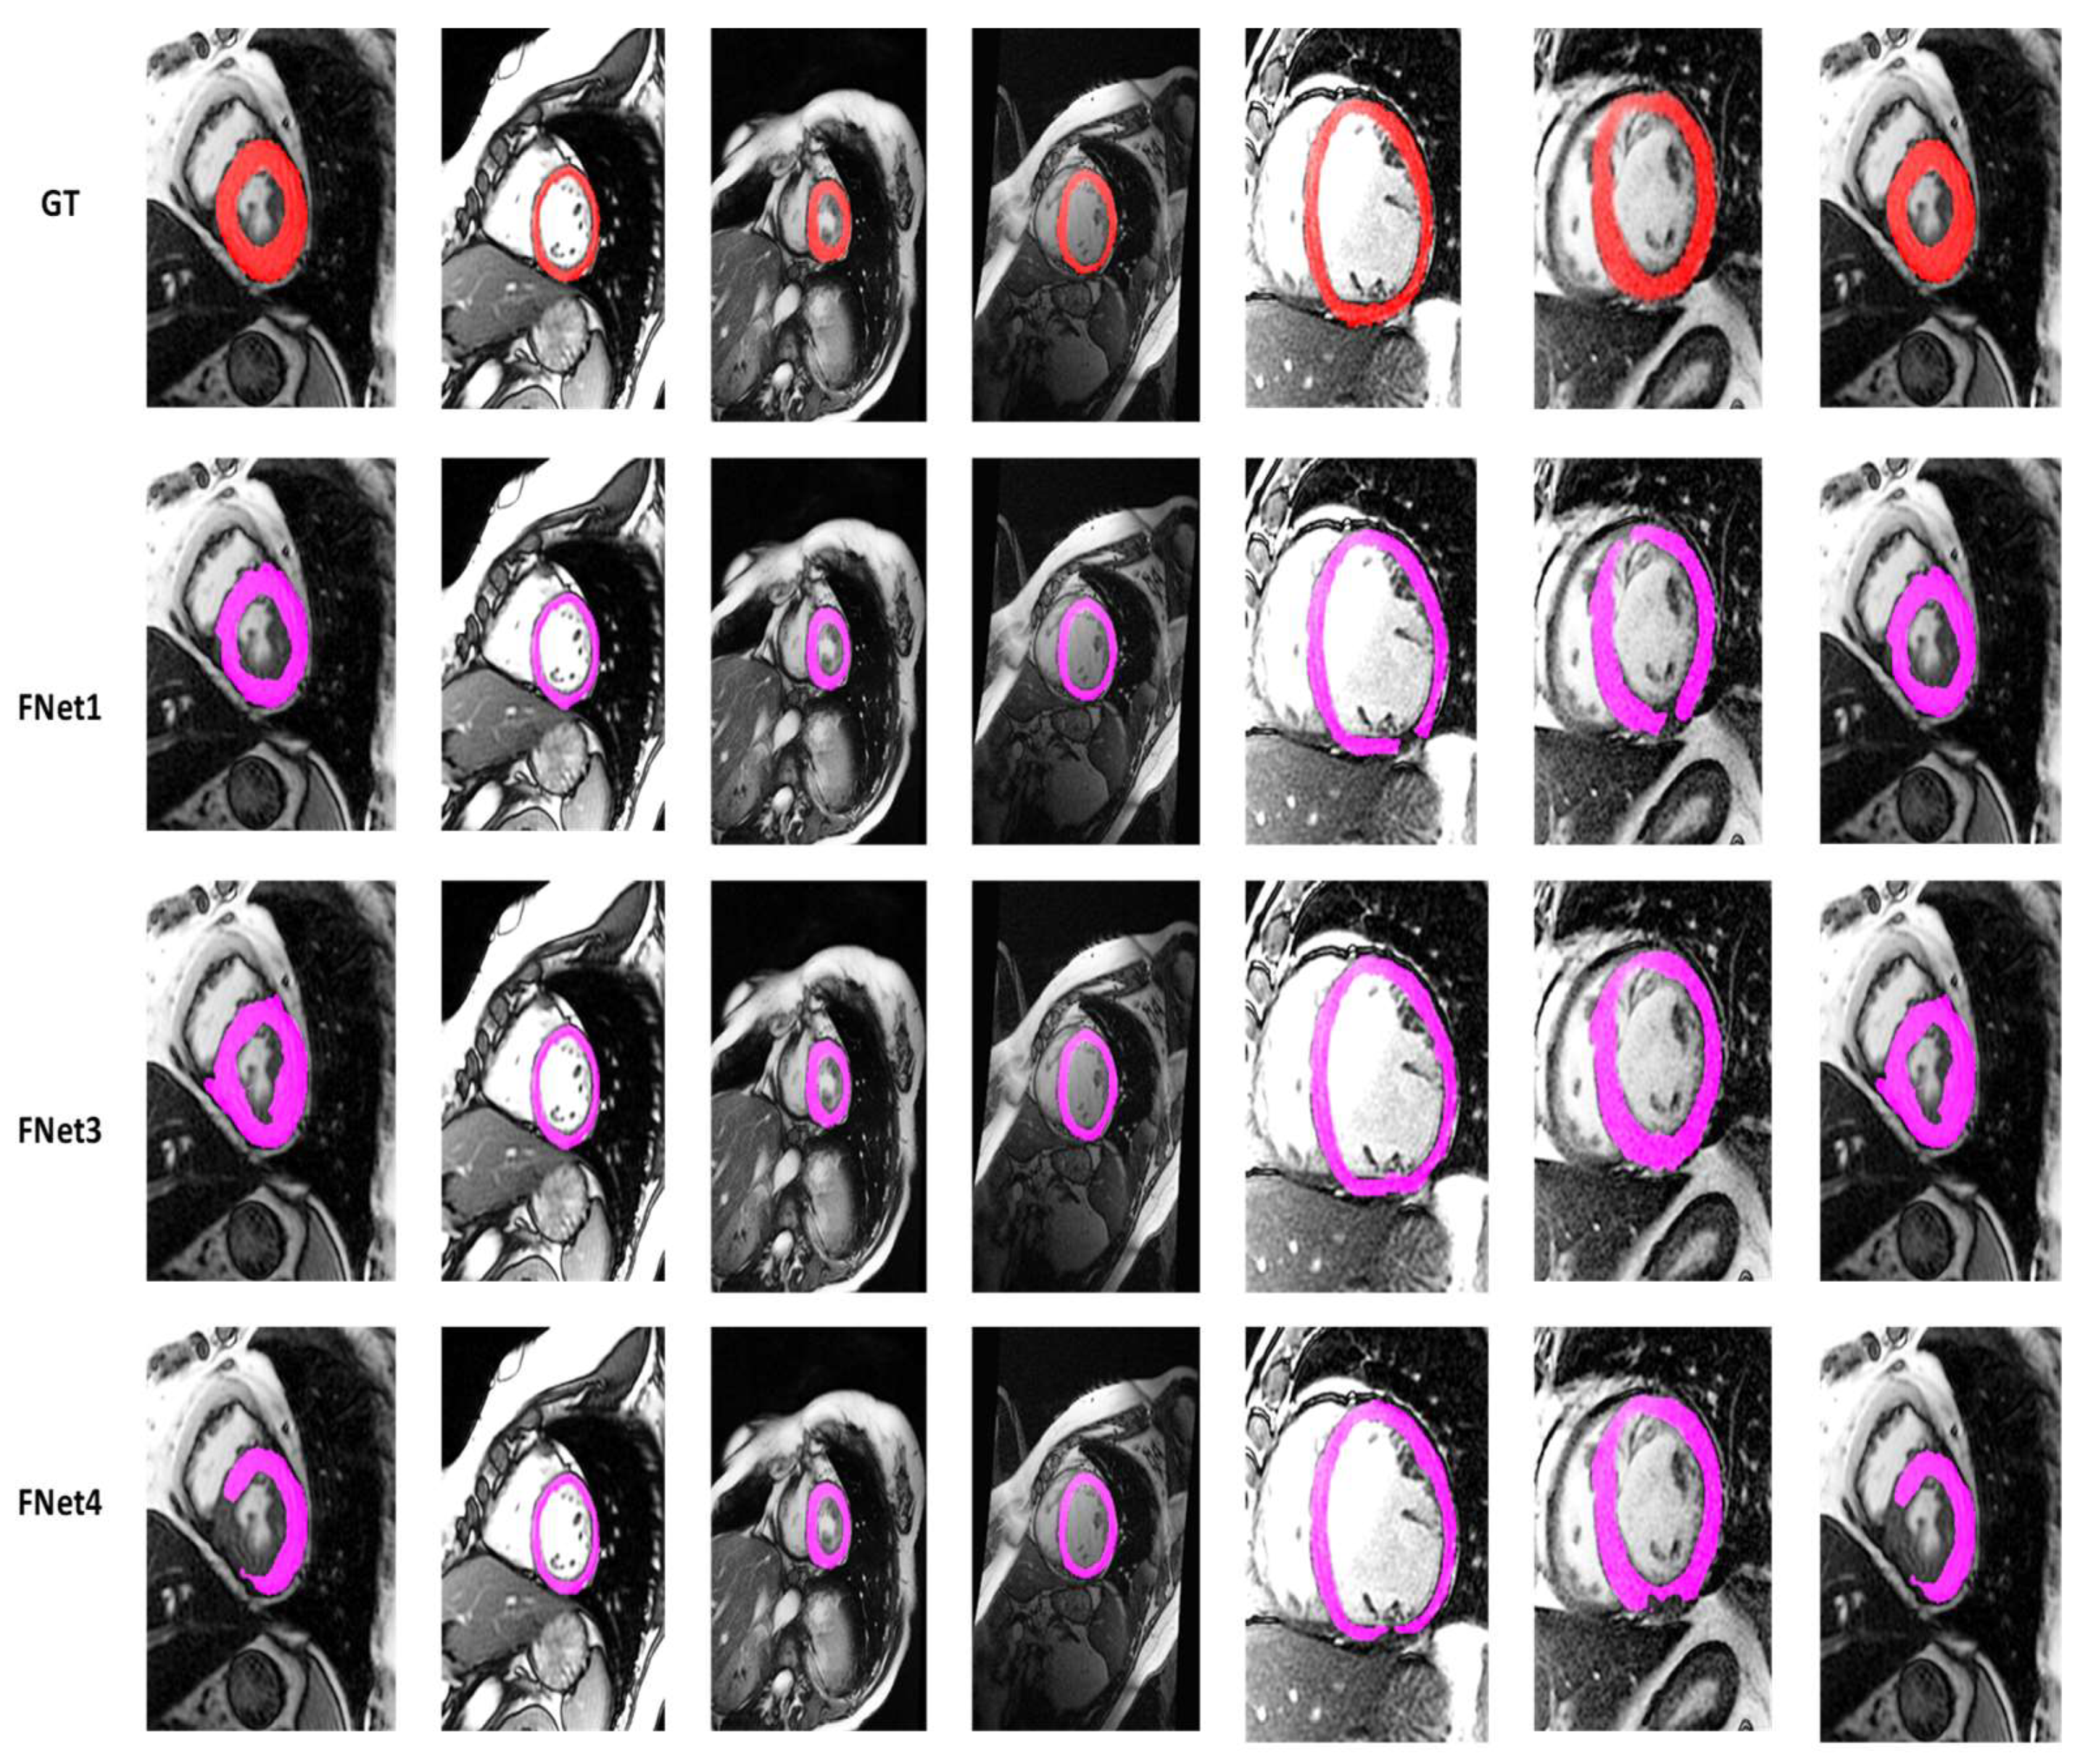

4.2. Visualization Segmentation Results